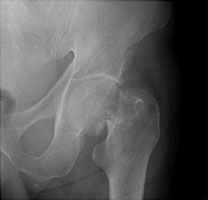

Femoral neck fractures also result from falls, especially in elderly and osteoporotic females. They are associated with radial and humeral fractures. The Garden classification is widely used to categorize these fractures. Garden I is an incomplete fracture through the femoral neck while with Garden II, the fracture is complete. With Garden III fractures, there is impaction, and with Garden IV, the femoral neck is superiorly migrated relative to the femoral head. Garden IV fractures have the highest risk of avascular necrosis.

A | AP view reveals a Garden II fracture of the left hip. |